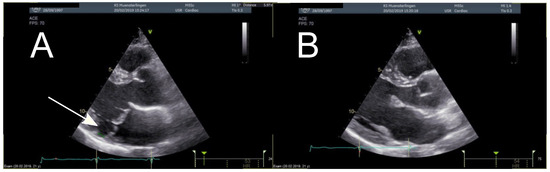

Congenital Left Ventricular Diverticulum in an Asymptomatic Patient: Multi-Modal Evaluation

by Negro Alessandro, Carballo David, Noble Stéphane and Müller Hajo

Congenital left ventricular diverticula are rare cardiac malformations. Few data are available regarding their prevalence, which is estimated to be around 0.04% and 0.7%, according to retrospective series. In our case a diverticular apical lesion of the left ventricle was incidentally found on [...] Read more.

Congenital left ventricular diverticula are rare cardiac malformations. Few data are available regarding their prevalence, which is estimated to be around 0.04% and 0.7%, according to retrospective series. In our case a diverticular apical lesion of the left ventricle was incidentally found on an urgent thoracic computed tomography scan, performed to rule out abdominal aortic rupture. A thorough evaluation with echocardiography, coronary angiography, ventriculography and cardiac magnetic resonance imaging was performed. After discussion in our heart team, which took into consideration the lack of cardiac symptoms, the small size of the diverticulum and the absence of thrombus, we decided on a conservative option. Full article